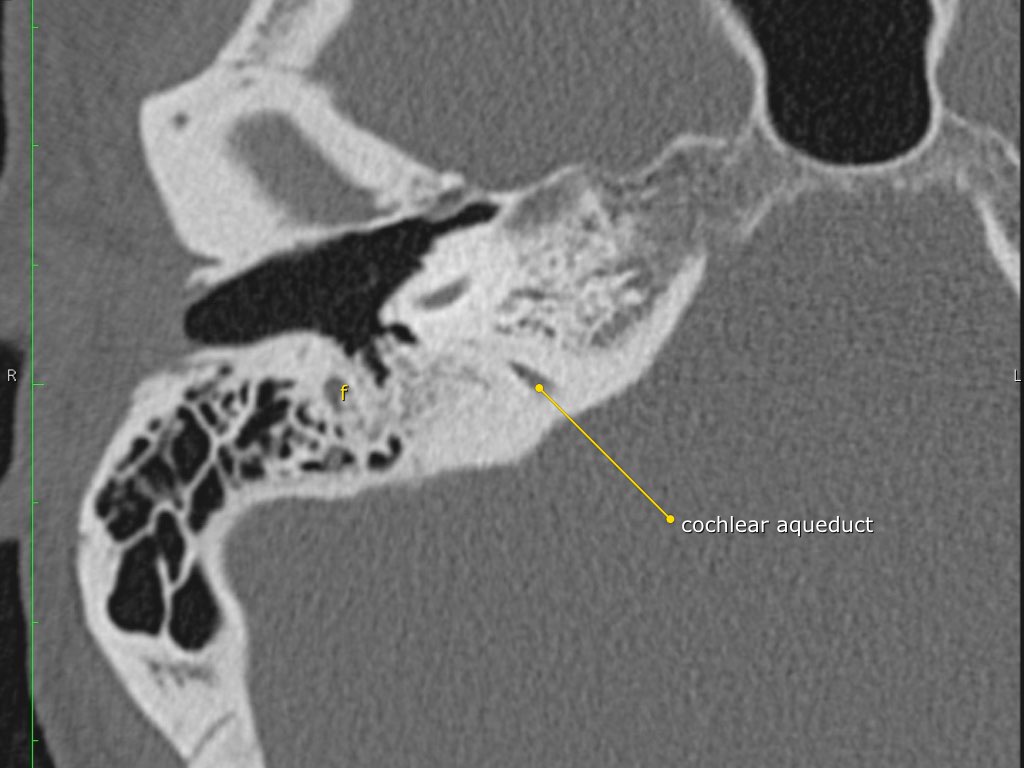

Trong bài tổng quan này, chúng tôi trình bày giải phẫu bình thường trên mặt phẳng cắt ngang (axial) và mặt phẳng cắt đứng ngang (coronal) của xương thái dương thông qua việc duyệt qua các hình ảnh.

Một số cấu trúc được thảo luận chi tiết hơn với trọng tâm là các bệnh lý liên quan.

Giải phẫu xương đá trên mặt phẳng cắt ngang (Axial)

Cuộn qua các hình ảnh.